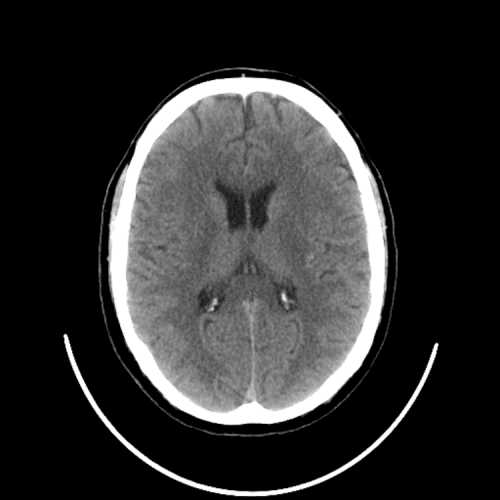

Case #3